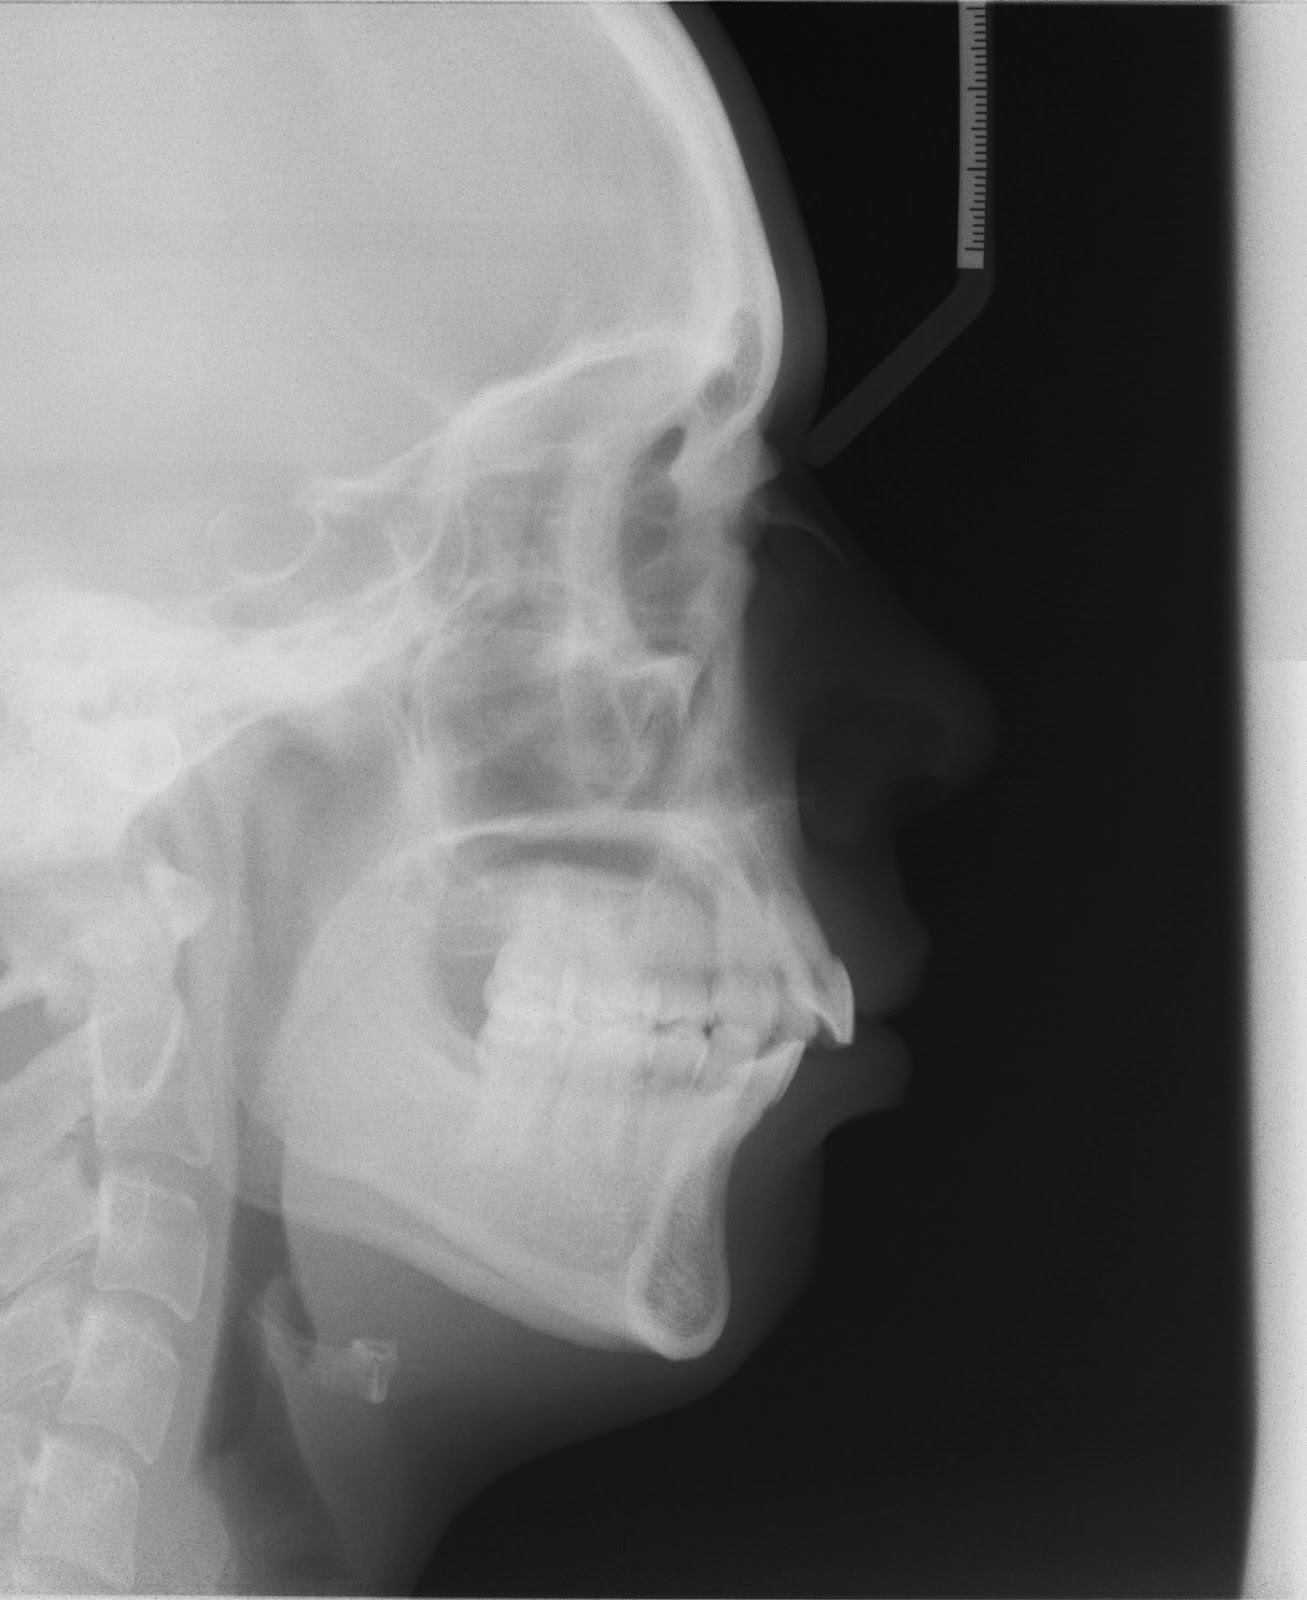

My Before & After XRays Jaw Surgery for mandibular advancement r/pics

Surviving Jaw Surgery Before&After X-Ray Of Jaw Surgery What part of my jaw is broken? Conventional radiography, nowadays, is of limited interest. jaw surgery corrects facial imbalances and allows the jaw bones to fit together correctly. choosing the proper imaging technique is essential. It provides a detailed view of the jawbone,. If the jaw is not lined up properly, it may lead to pain when chewing. X-Ray Of Jaw Surgery.